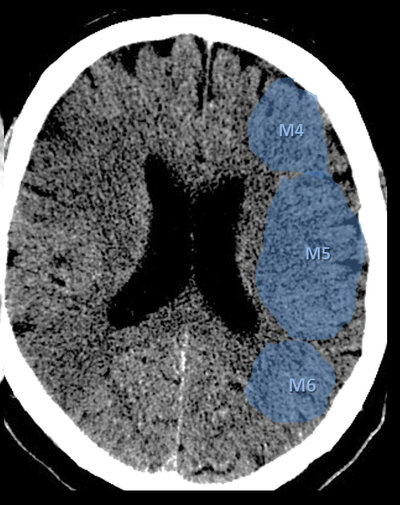

Coupe supra-ganglionnaire (corona radiata)

ASPECTS — Coupe supra-ganglionnaire : M4, M5, M6

M4 = ACM antérieur · M5 = ACM latéral · M6 = ACM postérieur